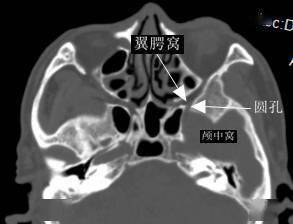

翼腭窝ct

翼腭窝的ct影像解剖